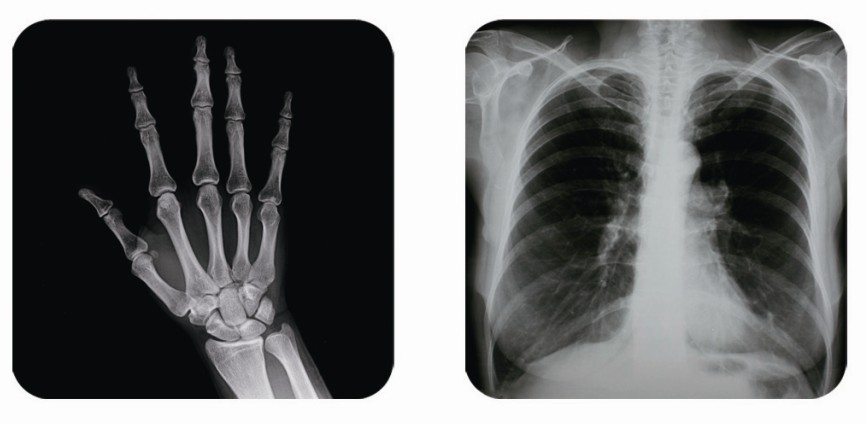

傳統(tǒng)胃腸造影檢查,病變顯示率低,輻射劑量大。普朗醫(yī)療器械公司生產(chǎn)的幾款多功能腸胃造影x光機,更能滿足不同等級不同規(guī)模的大小醫(yī)院選擇,從臨床及科研都很好。尤其最新的PLD8800多功能腸胃造影x光機用途更為廣泛。多功能腸胃造影x光機是目前各大醫(yī)院最普及的且用途最廣的一種X光機。普朗醫(yī)療的胃腸機功能多,簡便易用,能保證圖像質(zhì)量,該機采用高制式電視系統(tǒng),優(yōu)秀的數(shù)字化系統(tǒng)能使多功能腸胃造影x光機的性能得到提高,應(yīng)用范圍獲得極大的拓寬。

1、一般應(yīng)用:數(shù)字透視,動態(tài)及多方位觀察器官病變,圖像更清晰,并可保留末幀圖像;既可使用暗盒完成常規(guī)X線拍片,這是其最大的優(yōu)勢,拍片質(zhì)量大大提高。